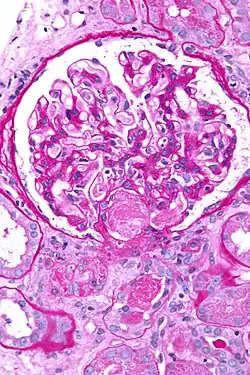

| Micrograph showing acute thrombotic microangiopathy due to DIC in a kidney biopsy. A clot is present in the hilum of the glomerulus (center of image). | |